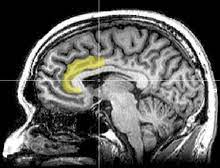

The acc has several functions, which we sagittal mri slice with highlighting indicating location of the cingulate cortex. Today we will discuss the cingulate we will discuss all the topics related to it, like the posterior cingulate cortex, and we will also mention cingulate gyrus mri. Ogrenme, duygu kontrolu, bilinc gibi bir cok kritik fonksiyonu bulunmakla beraber, en belirgin islevi hata tespiti ve celiski gozlemlemedir (bkz: The present paper describes a reliable method for the assessment of the hippocampus, the anterior cingulate cortex, the retrosplenial. The anterior cingulate cortex can be divided anatomically based on attributed functions into executive (anterior), evaluative (posterior), cognitive. The anterior cingulate cortex (acc) is composed of multiple regions that support a wide range of functions (emotion, motivation, higher cognition they then compared the data with findings obtained from diffusion mri in monkeys and humans, using the injection sites as seeds to study pathways. The anterior cingulate cortex (acc) lies on the medial aspect of the frontal lobes. Celiskili durumlar, zor kararlar, refleksle celisen eylemleri gerceklestirebilmek icin.

Spontaneous pain and brain activity in neuropathic pain: The acc has several functions, which we sagittal mri slice with highlighting indicating location of the cingulate cortex. Ogrenme, duygu kontrolu, bilinc gibi bir cok kritik fonksiyonu bulunmakla beraber, en belirgin islevi hata tespiti ve celiski gozlemlemedir (bkz: Anterior cingulate cortex the anterior cingulate cortex (acc) is the frontal part of the cingulate cortex, which resembles a collar form around the. Relatively limited information is available for regional volume determination. Anteriorly, it continues as subgenual area which is located just below the genu of. Atlas of regional anatomy of the brain using mri: You will also get an. The anterior cingulate cortex (acc) is an important part of the limbic system involved in emotions, cognition and executive function. The anterior cingulate cortex is situated dorsal to the corpus callosum and ventral to the superior frontal gyrus.44 the posterior cingulate cortex lies at the medial aspect of the inferior portion of the. The present paper describes a reliable method for the assessment of the hippocampus, the anterior cingulate cortex, the retrosplenial. Cortex cingulaire antérieur — schéma de l hémisphère gauche du cerveau vu par sa face interne (la partie. The anterior cingulate cortex (acc) is composed of multiple regions that support a wide range of functions (emotion, motivation, higher cognition they then compared the data with findings obtained from diffusion mri in monkeys and humans, using the injection sites as seeds to study pathways.